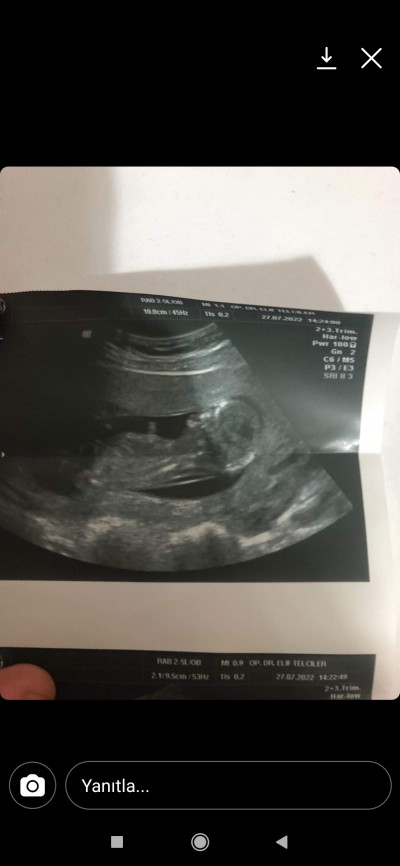

Cinsiyet tahminde buluna bilirmisiniz güzel anneler

Merhaba 14haftaligim sorum yukarda

Gebelik haftası

Yapısı erkek bebeğe benziyor saglikla alın kucağınıza:)

Teşekkür ederim doktor tahmin etdi bide haftası küçük olduğundan paylaşdım belki bilgili anneler iyi bilir diye

Teşekkür ederim doktor tahmin etdi bide haftası küçük olduğundan paylaşdım belki bilgili anneler iyi bilir diye sizde sağ salım.alin kucaginiza bebeklerinizi inşallah

Erkek mi tahmin etti

Kız mı doktorunuz tahmini neydi

Evet kız dedi canim

Kiz hissetttim canim